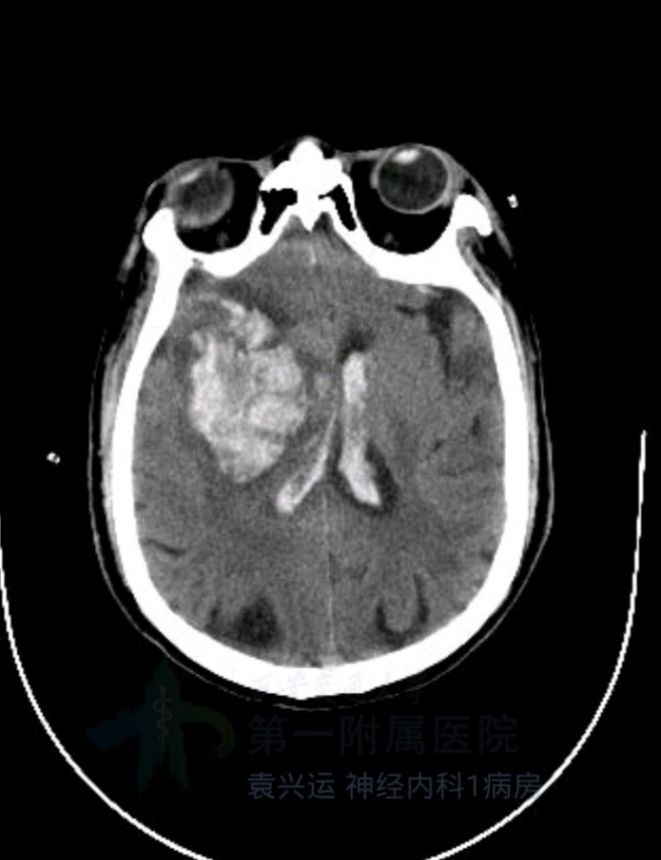

术后第3天,患者突然意识丧失,呼叫无反应,刺激右侧肢体无反应,左侧可见回缩,紧急头颅CT提示左侧半球大量脑出血并破入脑室,很快左侧瞳孔散大,深昏迷,家属拒绝行开颅血肿清除术,自动出院。

术后3天CT: